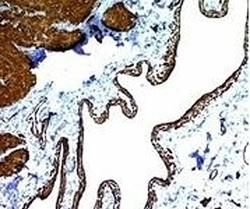

- Formalin-fixed, paraffin-embedded human colon carcinoma stained with alpha Smooth Muscle Actin antibody (ACTA2/791). This image was taken for the unmodified form of this product. Other forms have not been tested.

- Formalin-fixed, paraffin-embedded human colon carcinoma stained with alpha Smooth Muscle Actin antibody (ACTA2/791). This image was taken for the unmodified form of this product. Other forms have not been tested.